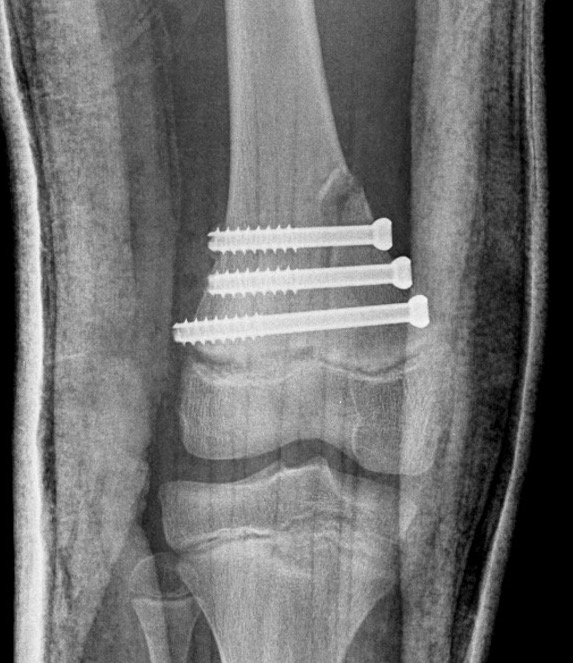

Salter Harris Type II with large Thurston Holland fragement

Distal Femur Salter Harris 2Distal Femur Salter Harris 2

Technique

AO foundation screw fixation Salter Harris Type II

Reduction

- attempt closed

- may be periosteum blocked on tension / medial side

Medial subvastus approach to knee

- identify Thurston-Holland fragment

- physeal sparing metaphyseal screws

Distal Femur SH2 ORIFDistal Femur SH2 ORIFDistal Femur SH2 Lateral